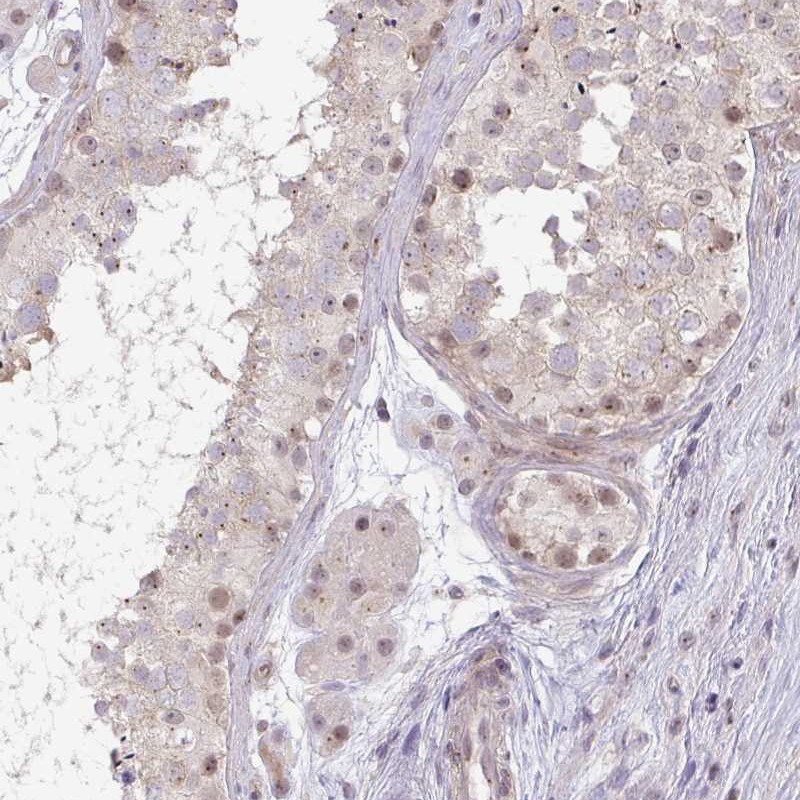

Immunohistochemical staining of human testis shows weak nuclear and cytoplasmic positivity in cells in seminiferus ducts.